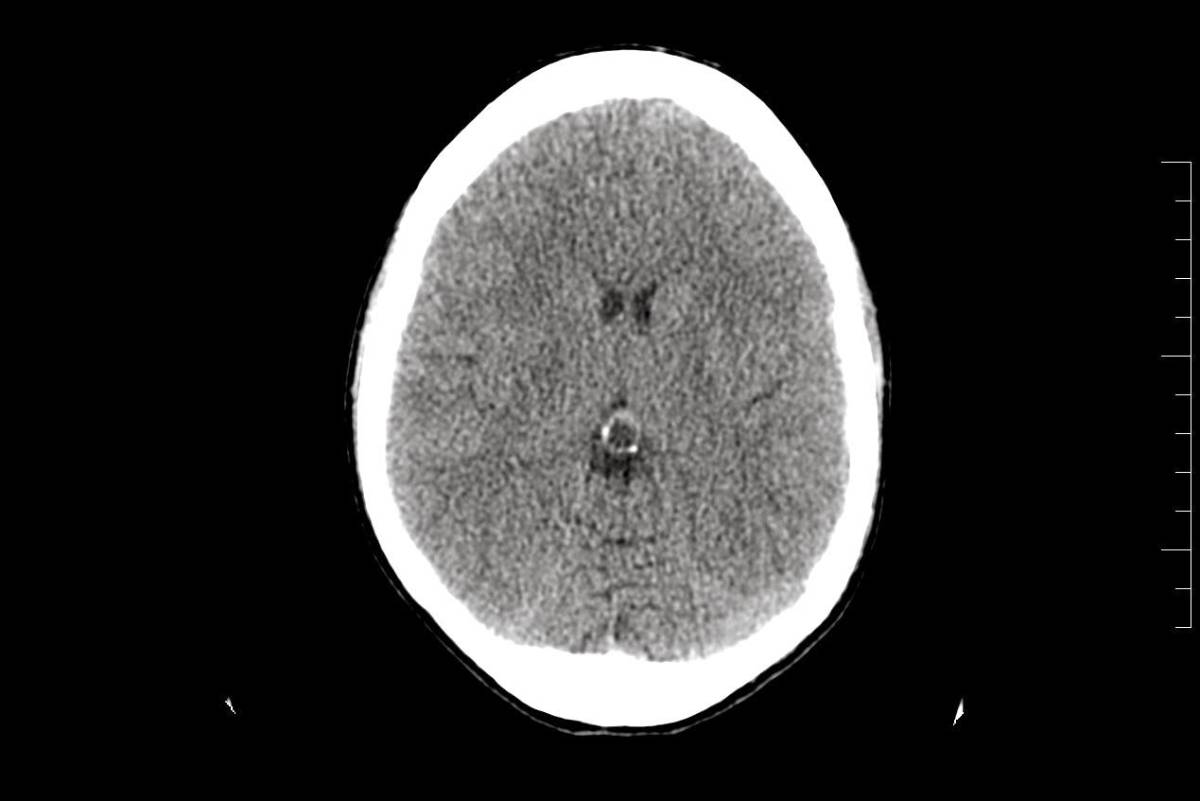

Cuando por fin le hicieron los estudios, éstos revelaron un pequeño tumor benigno en la glándula pineal, pero los doctores aseguraron que no tenía relación con su dolencia. Poco después lo regresaron al hospital debido al incremento de dolor en la cabeza acompañada de vómito. Como no podían operar el tumor lo sometieron a una punción lumbar.